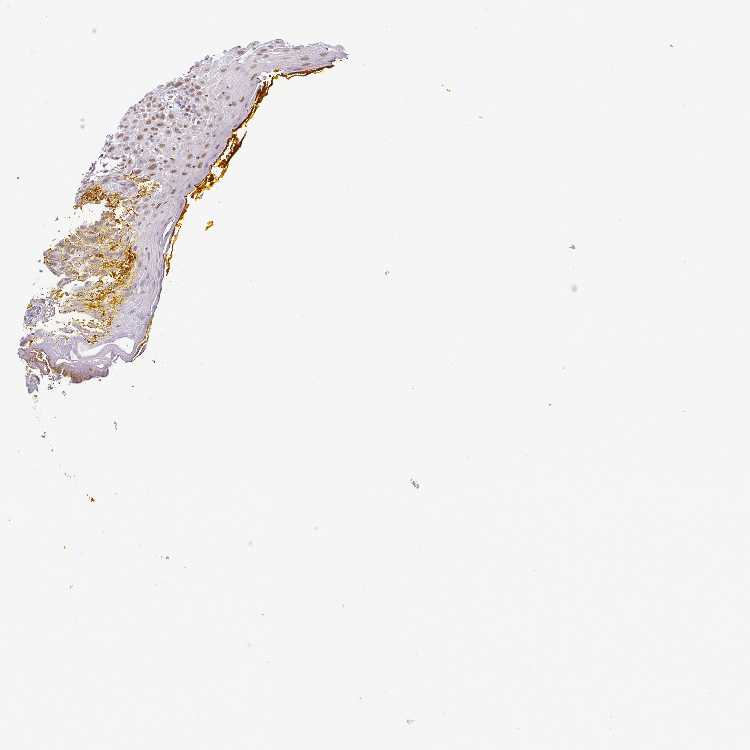

TISSUE PRIMARY DATA ORAL MUCOSA Show tissue menu

ORAL MUCOSA - Antibody stainingi

Antibody staining in the annotated cell types in the current human tissue is reported as not detected, low, medium, or high, based on conventional immunohistochemistry profiling in selected tissues. This score is based on the combination of the staining intensity and fraction of stained cells.

Each image is clickable and will lead to virtual microscopy that enables deeper exploration of all samples and also displays staining intensity scores, fraction scores and subcellular localization as well as patient and tissue information for each sample.

Antibody HPA011318Antibody HPA054041

Squamous epithelial cells Not detectedMedium